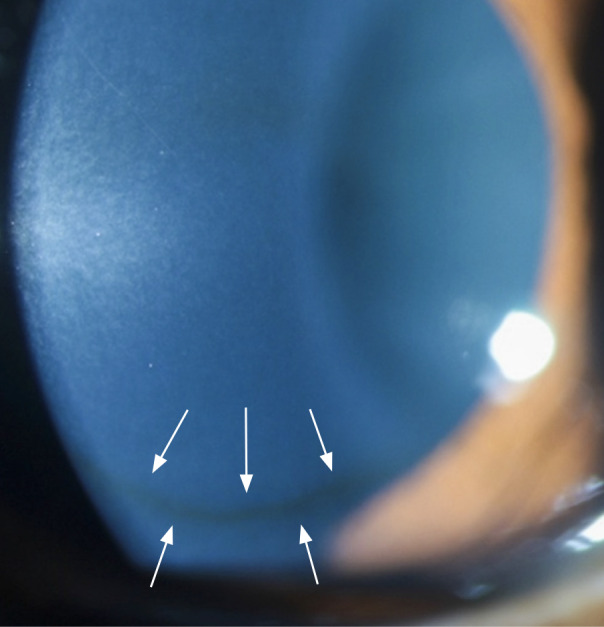

Keratoconus: an introduction.